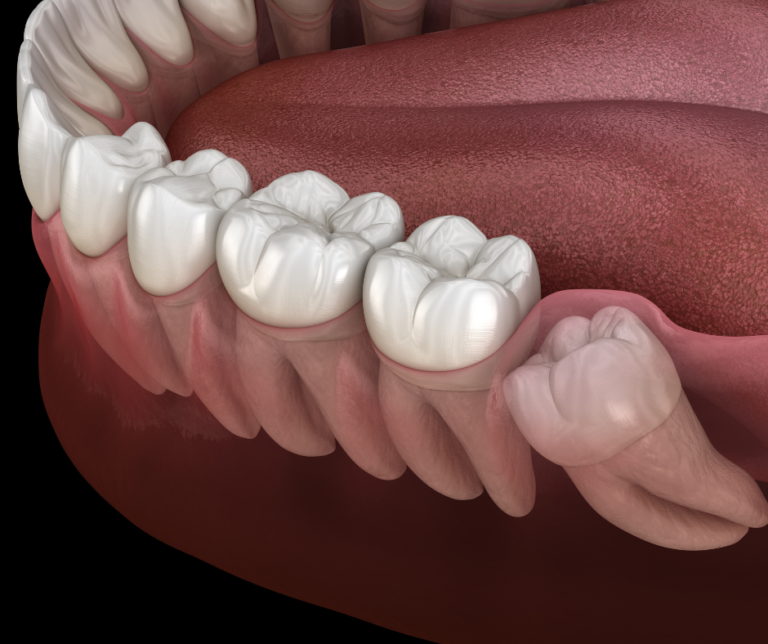

Wisdom teeth are the last teeth that develop in your jaws, so there is often not enough space for the wisdom tooth to grow fully to the correct position in your mouth. Wisdom teeth in malay usually erupts between age 17 to 25 years old.

When wisdom tooth does not grow into their correct position and becomes partially covered by the gums or impacted against the adjacent molar tooth, it can cause a variety of issues.